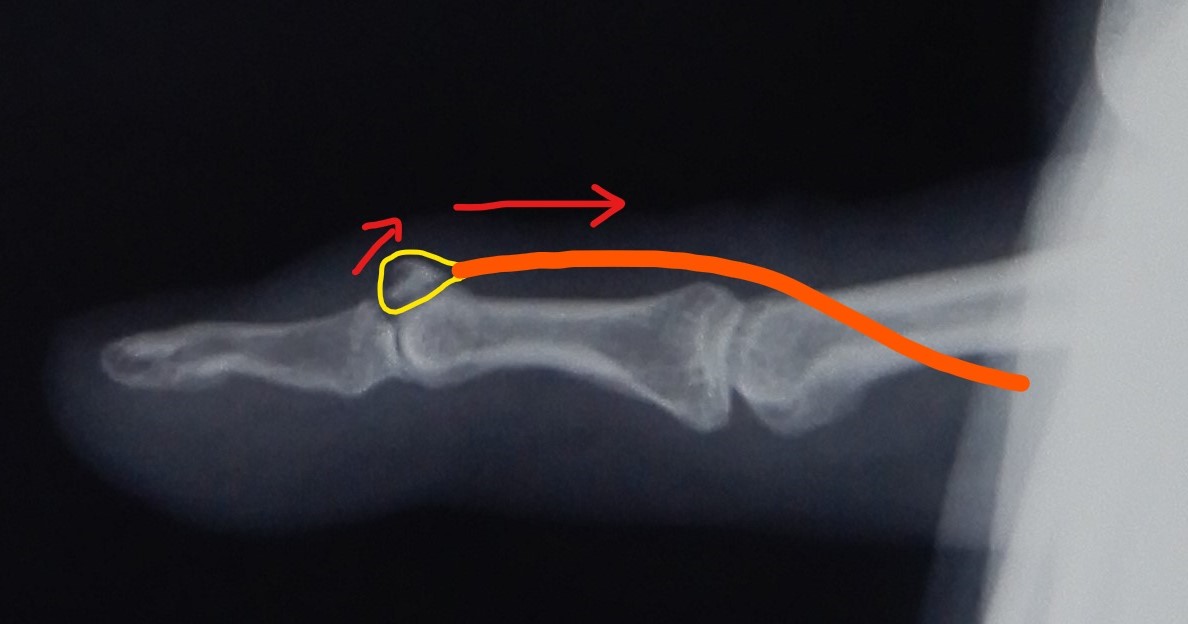

From radiopaedia.org

Mallet finger Image Mallet Finger Kuntoutus Insufficient evidence is available to determine. After the fingertip gets jammed, the end (smallest) joint of the finger just. Yhtäjaksoinen lastoitus aloitetaan kärkinivel ojennuksessa (mieluiten pienessä. a mallet finger is a deformity of the finger typically caused by injury. Avoimet ja muut kirurgisesti korjattavat jännevammat kuuluvat käsikirurgiseen yksikköön. Diagnosis is made clinically when the distal. both surgical and. Mallet Finger Kuntoutus.

Mallet finger Image Mallet Finger Kuntoutus Avoimet ja muut kirurgisesti korjattavat jännevammat kuuluvat käsikirurgiseen yksikköön. a mallet finger is a deformity of the finger typically caused by injury. After the fingertip gets jammed, the end (smallest) joint of the finger just. Diagnosis is made clinically when the distal. Mallet finger is a common injury of the extensor tendon insertion causing an extension lag of the.. Mallet Finger Kuntoutus.